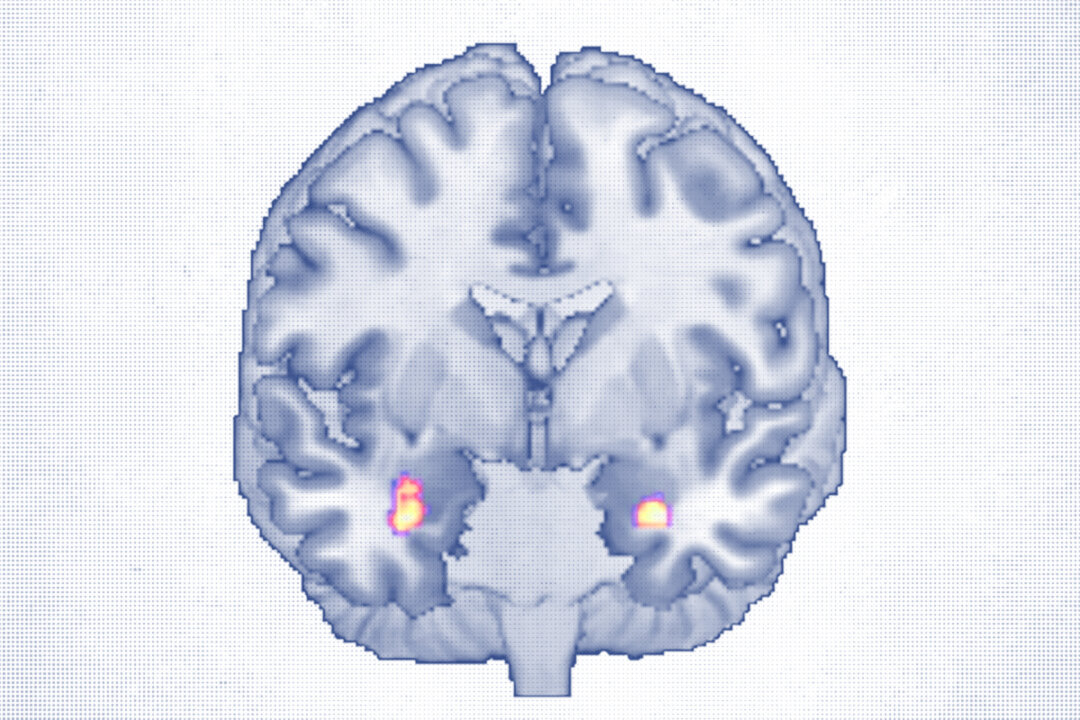

The study followed 30 adults, ages 18 to 65, with major depressive disorder who received about 20 CBT sessions over 40 weeks. High-resolution MRI scans before and after treatment revealed increased gray matter volume in the amygdala, a key region for emotional processing, and the anterior hippocampus, which is involved in memory and mood regulation.

Both areas are known to shrink in people with depression, so growth here may signal recovery, the researchers noted.

Increased gray matter in the amygdala was correlated with a greater ability to perceive emotions, particularly one’s own, Redlich said.